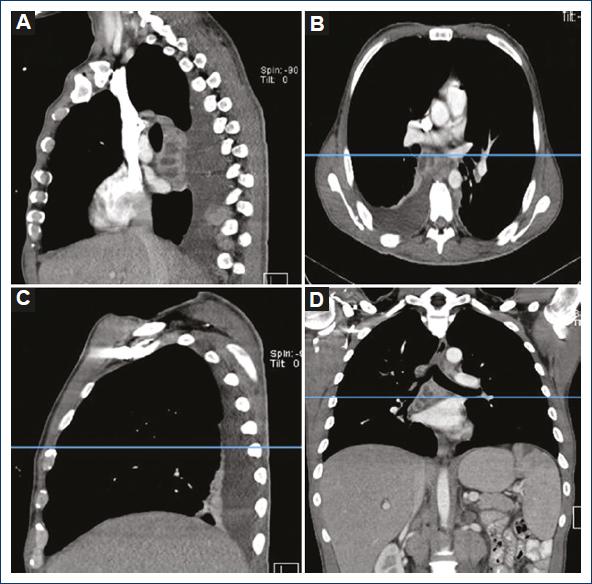

We evaluated 25 patients that we operated to drain the mediastinum for the diagnosis of mediastinitis, following the Estrera and Endo criteria, at the Hospital General de México “Dr. Eduardo Liceaga,” from August 1 2018 to July 31 2019. Ten (40%) were female patients and 15 (60%) were male patients. Twenty-one (84%) patients showed atelectasis and 4 (16%) did not have atelectasis. Of the patients that showed atelectasis, 17 (81%) were bilateral, 2 (9.5%) were right sided, and 2 (9.5%) were left sided. We also analyzed the occurrence of pleural effusion in this group. Fifteen (60%) patients had pleural effusion and 10 (40%) did not. Of the total patients with pleural effusion 11 (73.3%) were bilateral, 3 (20%) of the right side, and 1 (6.6%) of the left side (Figs. 1-3).

Figure 3 Patient with basal posterior segments atelectasis showing right basal posterior segment atelectasis, right pleural effusion, and right lymph nodes abscess suggesting lymph inflammation as a cause of atelectasis. A: sagittal plane left hemithorax. B: axial plane. C: sagittal plane right hemithorax. D: coronal plane.

A few studies mention the presence of atelectasis when the diagnosis is mediastinitis such as the one of Asrar3 Haz clic o pulse aquí para escribir texto.that proposes as a cause of atelectasis the inflammation of the hilar lymphadenopathy due to infection. At our study, we found a patient with a couple of right hilar nodes affected by inflammation that showed atelectasis and pleural effusion only at the right side, without any of both findings in the left side.